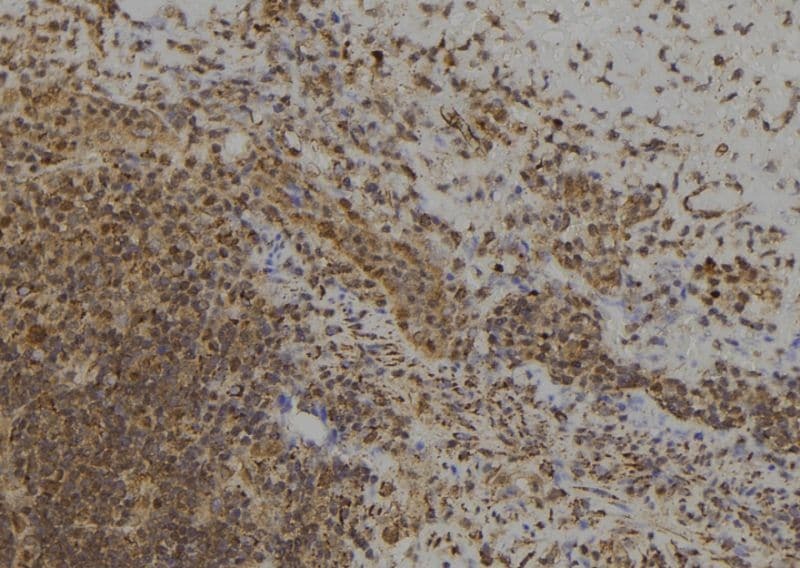

- Immunohistochemistry analysis of paraffin-embedded MAGED4 in human spleen tissue. Antigen retrieval was performed using citrate buffer. Samples were blocked with blocking buffer (1.5 hr, 22°C), incubated with MAGED4 polyclonal antibody (Product # PA5-100735) using a dilution of 1:100 (1.5 hr, 22°C), followed by HRP conjugated goat anti-rabbit.